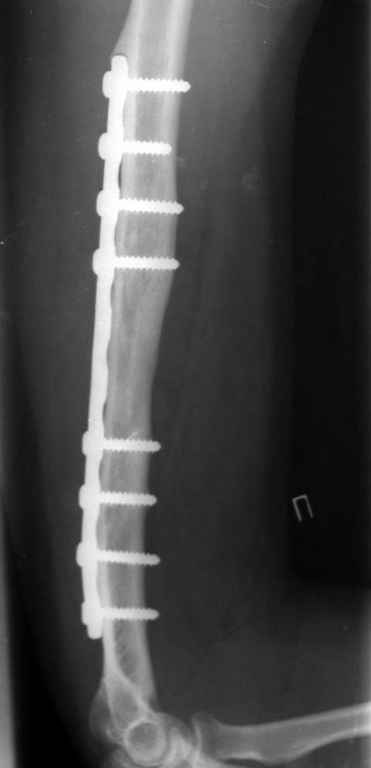

[Ortho] Ложный сустав плечевой кости

Владимир.Выделяем свои малоберцовую кость практически

полность.Выпиливаем замок там и тут. Синтез. Не типичный случай,но

перестраивается хорошо даже диафиз. рЕНТГЕН ПРИЛАГАЮ

Вложение не в текстовом формате было извлечено…

Имя     : Рисунок3.jpg

Тип     : image/jpeg

Размер  : 8856 байтов

Url     : http://weborto.net:8080/pipermail/ortho/attachments/20100208/ce18b105/attachment-0005.jpg